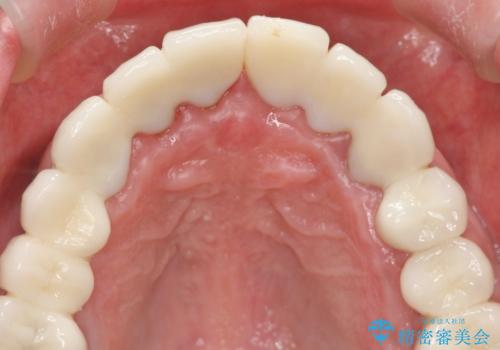

セラミッククラウンを除去し仮歯を装着し、歯周外科手術を行い歯ぐきの状態を改善したのち、適合の良いセラミッククラウンを再作製をする治療計画としました。

見た目の良いクラウンが装着されていても、歯ぐきの状態が悪ければ違和感や歯ぐきの腫れ、臭いの元となっていることが多く見られます。